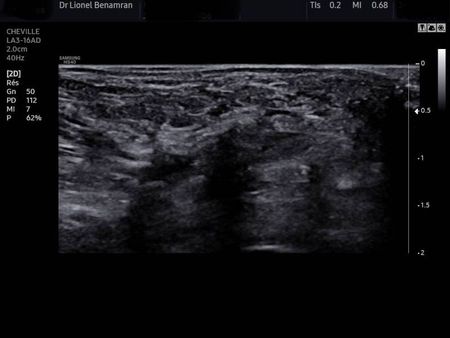

Écho graphie du névrome de Morton

Cas Clinique : Traitement du Névrome de Morton par Neurolyse Percutanée Échoguidée sous anesthésie locale en consultation

La neurolyse percutanée échoguidée permet de traiter efficacement le névrome de Morton avec une récupération rapide et indolore.